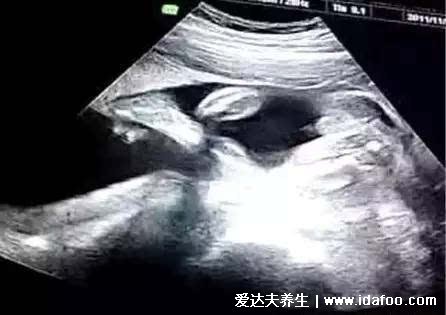

各位孕妈妈在怀孕的时候,是否是有上面的一些表现呢,这些说法是民间流传的一些说法,想要得知最准确的结果,实际上,只有在孩子出生之后才能得知的,除了症状之外,也有孕妈妈借助b超数据以及清宫表来看男女,不过大家也是不必过于认真了。

其实看孕囊很准两个数据

孕囊是胎儿还没有形成的时候的才有的,只在怀孕的早期才可以看到,在女性停经35天的时候是可以观察到的,大家需要去医院做个B超,大家是可以根据怀孕的阶段和孕囊的大小,看孩子是否是正常发育的.....